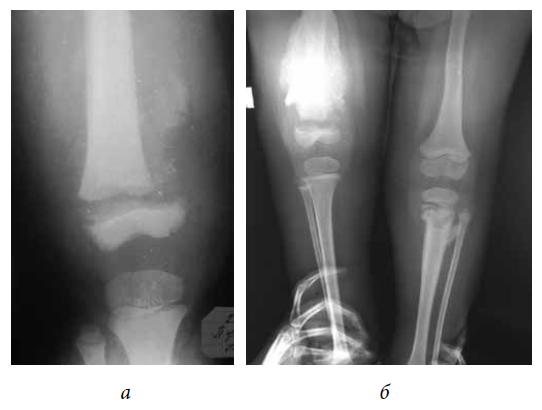

The radiological features of an atypical fracture of long tubular bones in pediatric patients with the consequences of spina bifidas include the absence of a fracture line, the presence of an excess periosteal reaction, and sclerosis at the fracture site (Fig. 2).

Fig. 2. Patient G. The diagnosis is the consequence of spina bifida. Neurosegmental level L1–L2. Osteoepiphysiolysis of the distal femoral epiphysis on the right: a — day 14 after injury; b —week 5 after injury, hypertrophic periosteal reaction

Hypertrophic callus was detected in 31 of 134 (23%) patients. In a retrospective analysis, it was revealed that the atypical nature of the X-ray pattern of the fracture in 10 patients required a bone biopsy to rule out osteogenic sarcoma, and in five patients, the excess callus was mistakenly interpreted as a manifestation of osteomyelitis. Knowledge of the radiological aspects of atypical fractures of the long tubular bones in patients with the consequences of spina bifidas enables us to conduct a correct differential diagnosis and develop appropriate treatment tactics.